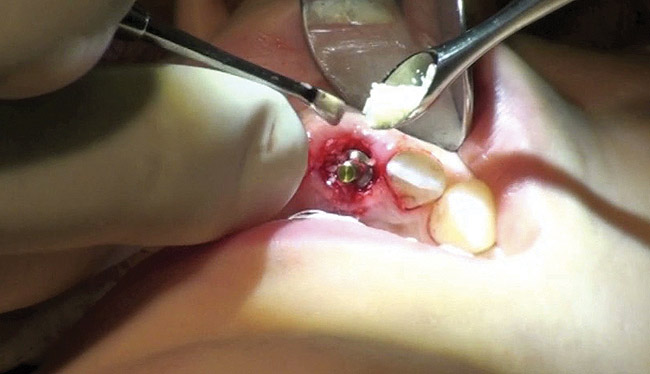

Figure 13  Initial osteotomy preparation with 2.1-mm precision drill, site No. 9. Priority level: 3.

Figure 13

The osteotomy was started slightly palatally in alignment with the surgical guide, using a 2.1-mm precision drill (Figure 13) and finalized with shaping drills under copious external irrigation with sterile water. Special attention was paid to overcorrecting the osteotomy preparation toward the palate, where the bone is denser. An implant in this area—especially a tapered implant, as was used here—will usually veer toward the facial surface during insertion. Using the surgical guide to superimpose the central axis of the implant on the previous location of the central incisor’s cingulum facilitates accurate positioning (Figure 14).